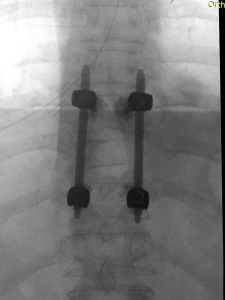

Παράδειγμα εξωσκληρίδιου όγκου: Ασθενής Άρρεν, 73 ετών, με γνωστή μεταστατική μάζα στον Θ10 σπόνδυλο, η οποίοα προκαλεί σημαντική στένωση του σπονδυλικού σωλήνα και πίεση επί του νωτιαίου μυελού. Διενεργήθη αποσυμπίεση του νωτιαίου μυελού και διαδερμική σπονδυλοδεσία/σπονδυλοπλαστική Θ9-Θ10. Μετεγχειρητικά ο ασθενής ανέφερε σημαντική πίεση του άλγους του και σημαντική βελτίωση της βάδισης.

(Προσωπικό Αρχείο Νευροχειρουργού Π. Σταυρινού)